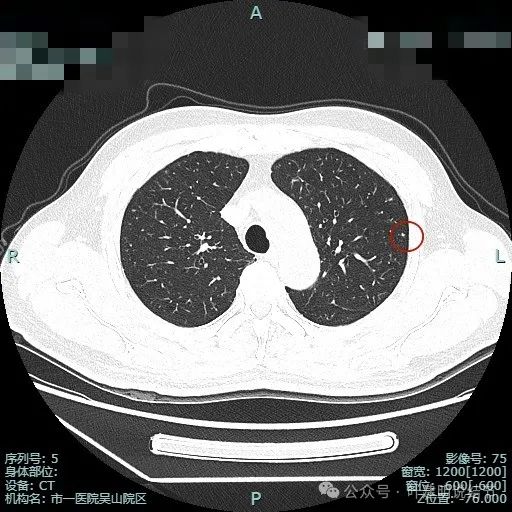

图片

次病灶术前定位,上图均是定位胶,结节太小,在其附近层面。